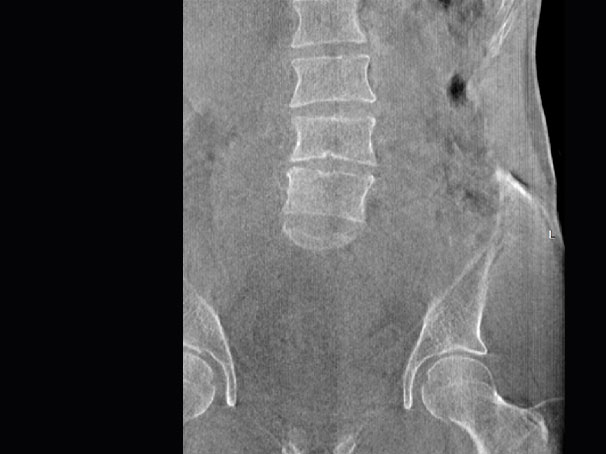

髋关节

腰椎

FOV 250mm

FOV 350mm